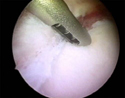

κινητοποίηση της βλάβης (αποκόλληση του επιχειλίου χόνδρου) (0.66MB)

επιχειλίος χόνδρος μετά απο την αποκατάσταση (0.25MB)

Βλάβη Bankart πριν και μετά απο την αποκατάσταση